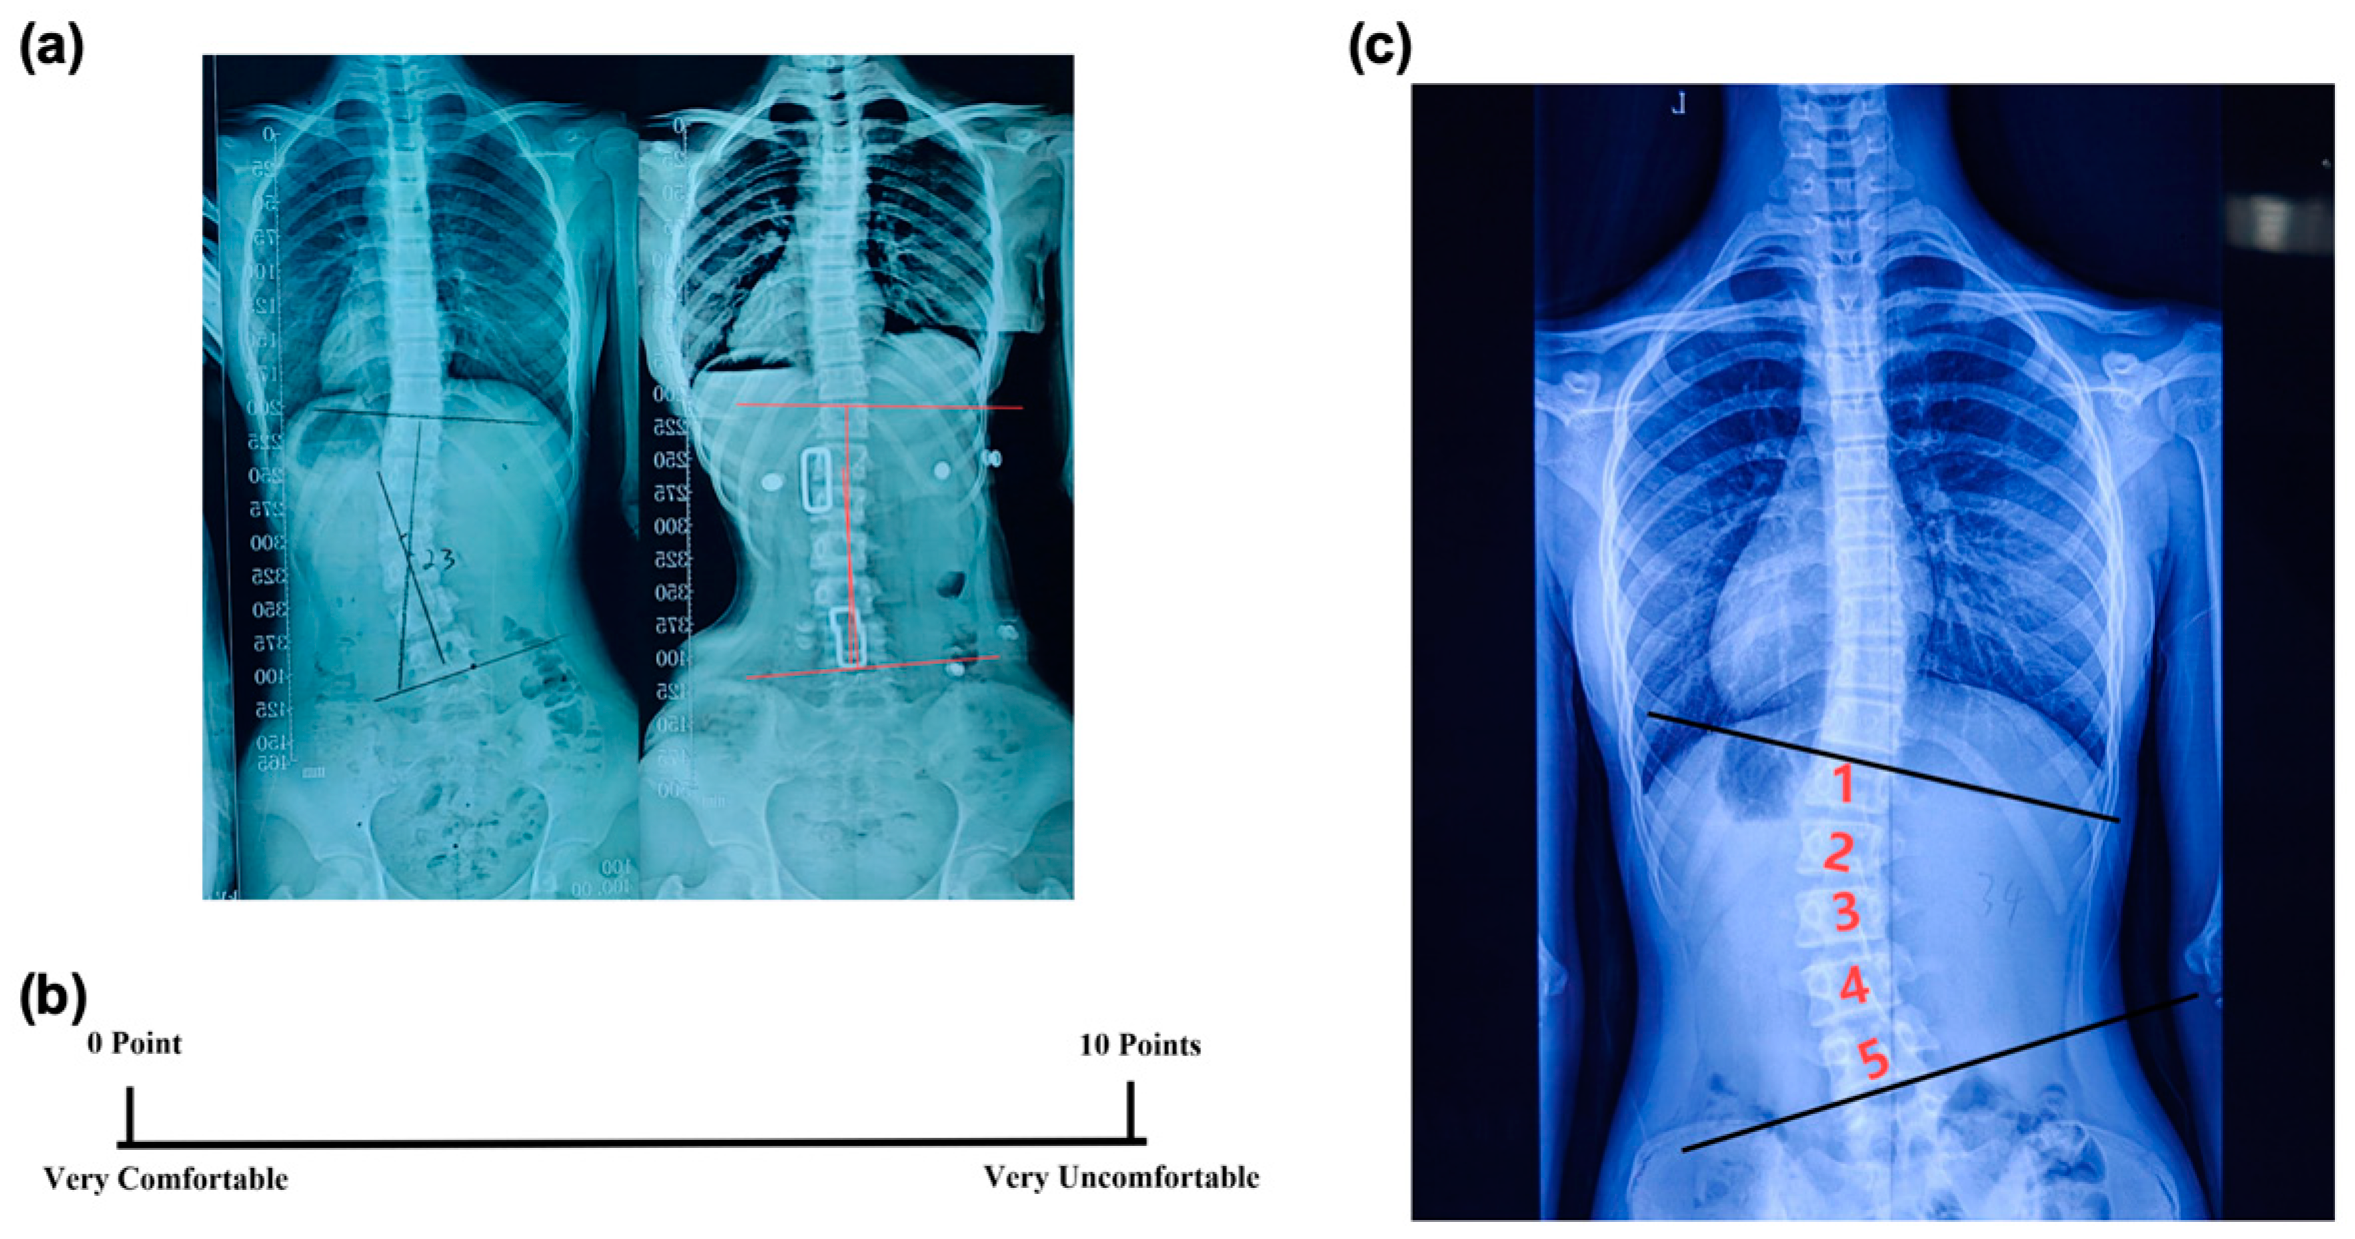

裁断済 脊椎脊髄病学 = PRINCIPLES OF SPINAL DISOR。脊椎・脊髄疾患の外科 第2版 | 飛驒一利, 小柳 泉 |本 | 通販。裁断済 脊椎脊髄病学 = PRINCIPLES OF SPINAL DISOR Textbook of。裁断済の商品です。Excessive Activation of TGFβ by Spinal Instability Causes。裁断の意味がわからない方は購入をご遠慮ください。イヤーノート 内科・外科編 2026 シリアルナンバー未使用。中に目立った書き込みはありませんが、ページが曲がっている部分があります。プロメテウス解剖学アトラス 第2版 3冊セット。写真でご確認ください。【裁断済】犬と猫とエキゾチック動物の臨床麻酔・疼痛管理学。読む分には問題ありませんでした。獣医 動物 専門書教科書セット。裁断済のため傷汚れありとしております。叡智の道 = THE KNOWING WAY : レムリアから伝わる神秘の教え…。佐川急便/日本郵便もしくは佐川急便/日本郵便で発送予定です。す*ち様 ドクターズルール425 : 医師の心得集。「脊椎脊髄病学 = PRINCIPLES OF SPINAL DISORDERS」岩崎 幹季定価: ¥ 15000#岩崎幹季 #岩崎_幹季 #本 #自然/医療・薬学・健康

• 裁断済 脊椎脊髄病学 = PRINCIPLES OF SPINAL DISOR

• 脊椎・脊髄疾患の外科 第2版 | 飛驒一利, 小柳 泉 |本 | 通販

• 裁断済 脊椎脊髄病学 = PRINCIPLES OF SPINAL DISOR Textbook of

• Excessive Activation of TGFβ by Spinal Instability Causes